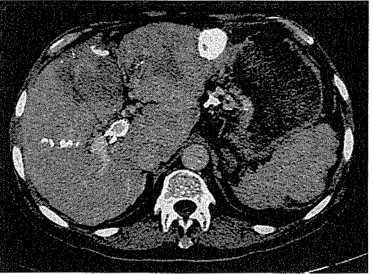

1.12.5.4四、诊断与鉴别诊断

1.12.5.5五、影像学检查

1.12.5.6六、放射介入治疗

1.12.5.7七、放射介入的疗效机制